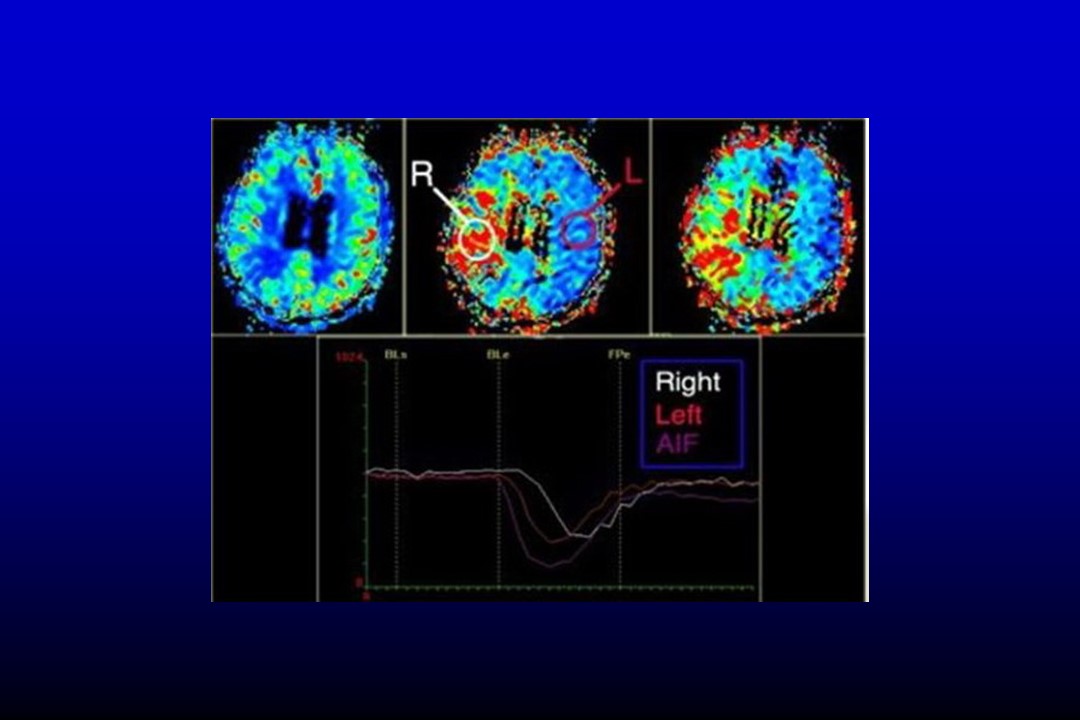

“脑缺血—急性脑梗死的影像学表现” 的相关文章